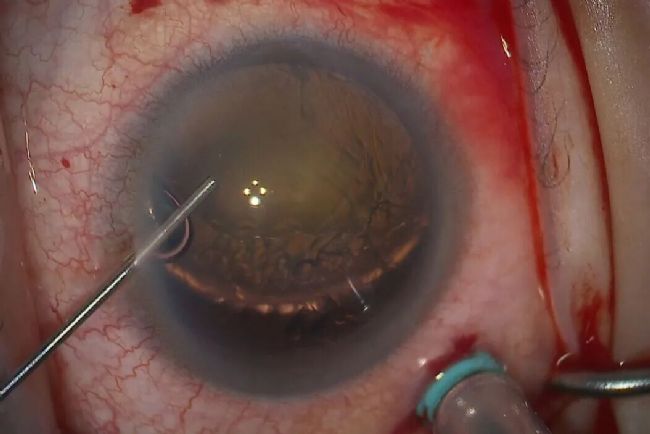

在白内障手术中具有重要作用,使眼科医生能够观察精细结构并进行精准操作。尤其当白内障发生脱位时,术者需准确评估其位置并制定安全有效的移除方案。

一名 56 岁男性突发右眼疼痛伴视力丧失。患者既往无外伤或手术史,左眼视力为 20/20。因前房玻璃体导致房角关闭而转诊。

手术目标是通过处理脱位性白内障,实现长期良好效果,避免未来发生晶状体再脱位。